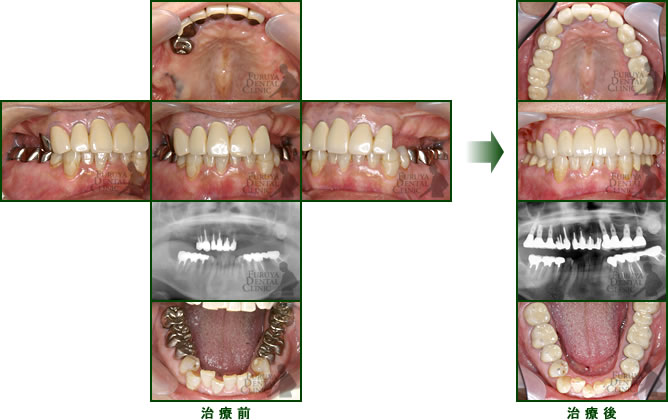

40代 女性

奥歯の入歯で我慢していましたが噛めないし、前歯が異常にすり減ってきたので全顎的治療を施しました。

20代の口腔内よりよくなったと喜んで頂いています。